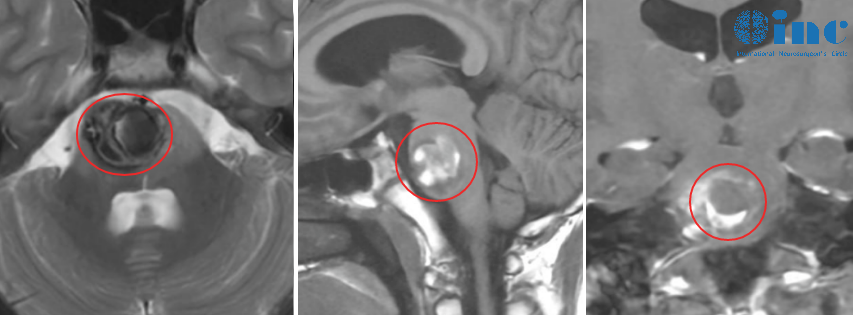

12岁男性患儿因频繁头痛恶心症状就诊,经磁共振检查发现脑干海绵状血管瘤。病灶位于脑干关键区域,初期经北京医院专家评估建议采取保守观察方案,患儿家属接受该建议并带患儿回家观察。

经过半年观察期,患儿出现双腿无力症状,复查核磁共振显示血管瘤少量出血。再次选择保守治疗方案后,症状暂时缓解。4个月后患儿出现左手无力表现,经当地及北京医院复查确诊为血管瘤二次出血。北京医疗团队建议手术治疗,但告知可能存在视神经损伤、吞咽功能障碍、语言能力受损及瘫痪等术后风险。

术后6个月随访复查时,核磁共振显示脑干区域存在异常信号,初步考虑海绵状血管瘤可能,引发家属担忧。经巴特朗菲教授远程随访确认,该异常信号实为含铁血黄素残留,属于巨大出血性内生性脑干病变的正常术后表现,并非活动性海绵状血管瘤复发或残留。